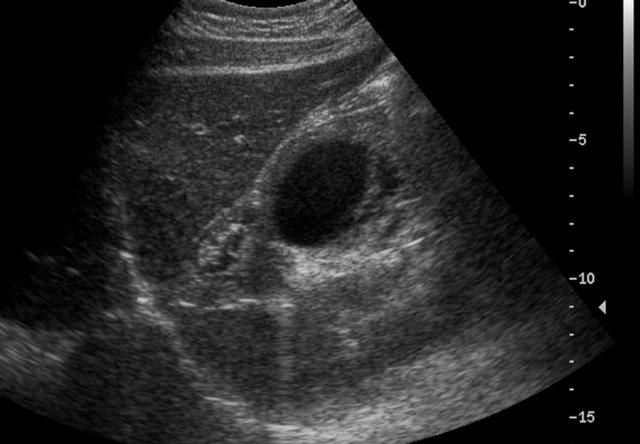

Đây là hình ảnh một nang được phát hiện trước sinh, được xác nhận sau khi sinh ở một bé gái sơ sinh.

Quan sát thấy một nang có mức dịch-dịch (fluid-fluid level).

Trong phẫu thuật, phát hiện xoắn buồng trứng trái.